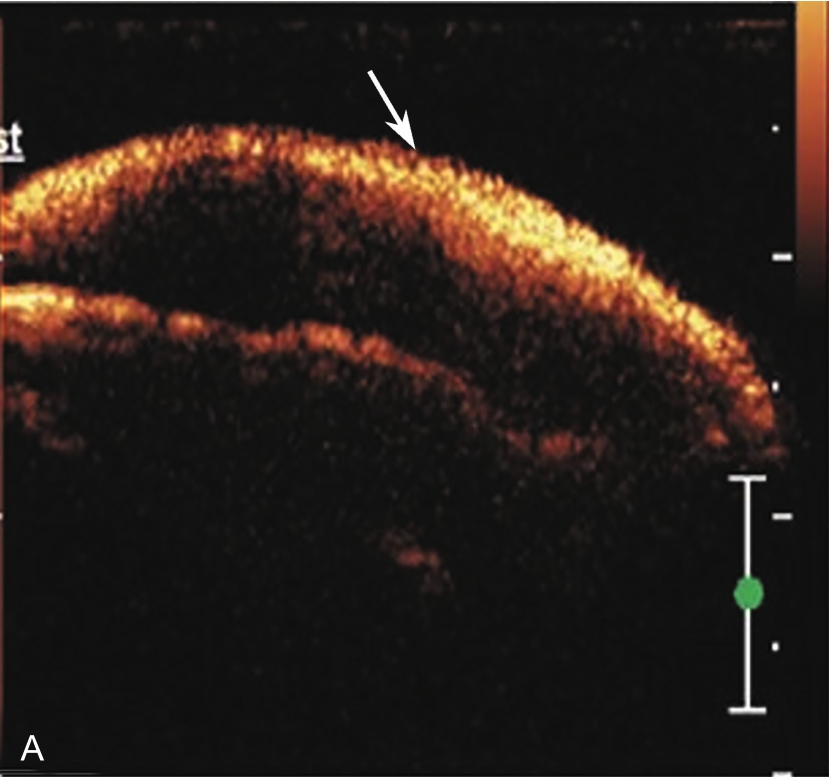

3.当肩袖回声不均匀,有可疑的滑囊面撕裂或全层撕裂,行超声引导下肩峰下-三角肌下滑囊造影检查,可提高对肩袖撕裂的诊断率。方法:将2~5ml生理盐水与0.5ml的超声造影剂混合后,注入肩峰下-三角肌下滑囊,无撕裂的滑囊呈线状高增强(图2-1-8),肩袖滑囊面部分撕裂可见造影剂混合液从滑囊进入肩袖肌腱内而未达肱骨头表面(图2-1-9),若观察到其进入肩关节腔或肱二头肌长头腱鞘,则诊断肩袖全层撕裂(图2-1-10)。

▲ 图2-1-8 超声引导下肩峰下-三角肌下滑囊造影图(一)

A.超声引导下滑囊内注入超声造影剂后,滑囊呈线状高增强(箭头);B.注入造影剂后的滑囊(箭头),冈上肌腱(SUP)连续性好,未见撕裂,HH:肱骨头